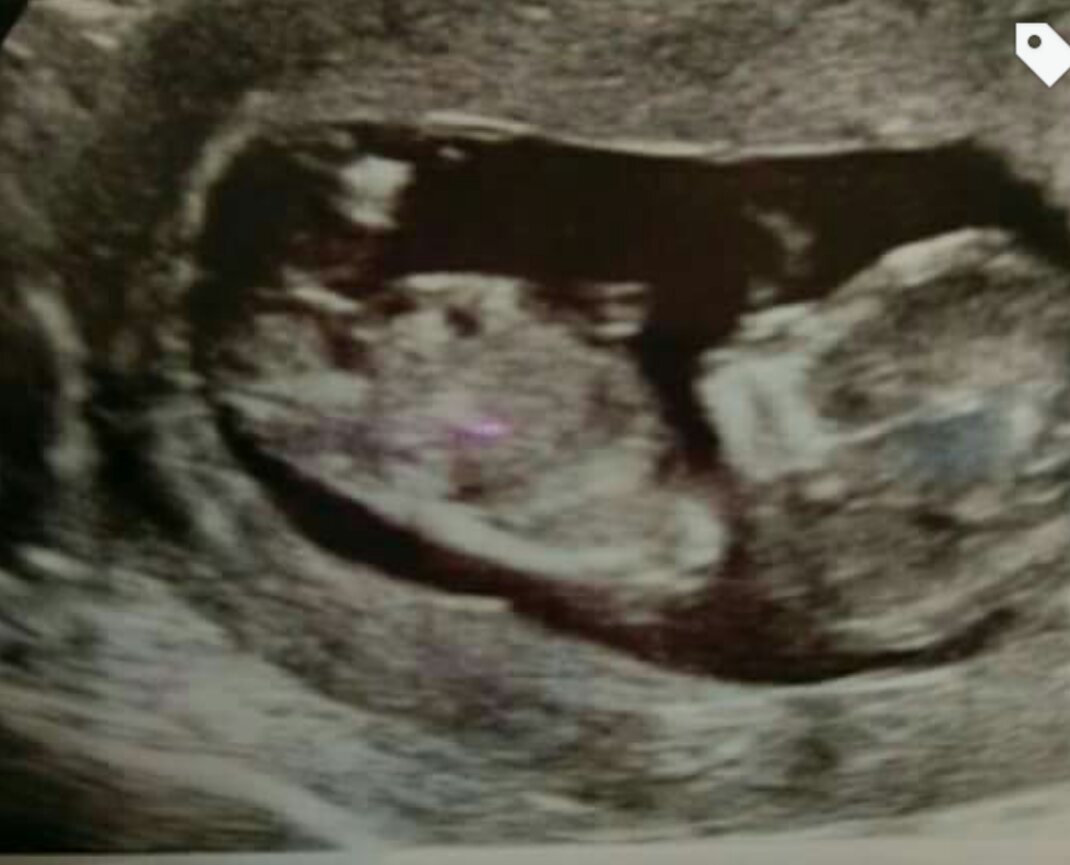

Hi all :-) this is my 12wk 1 day scan, any guesses would be appreciated!

Anymore side view pics? This one looks kind of girlie but there may be some stacking on the nub.

Tricky one isn't it? I don't have anymore side views, I do however have a 3d shot but the view isn't really suitable for looking at the nub angle as such. I think you can see the nub in it though but I have no clue whether it looks boy or girl!

Tricky shot. Maybe girl, but could also be boy.